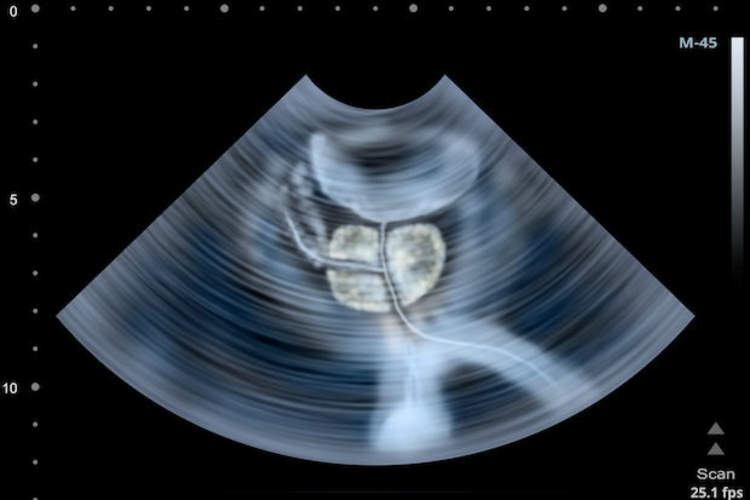

你对前列腺活检了解多少?

前列腺活检在门诊进行,大约需要20分钟,用于诊断或排除前列腺癌。这是我们的期望。